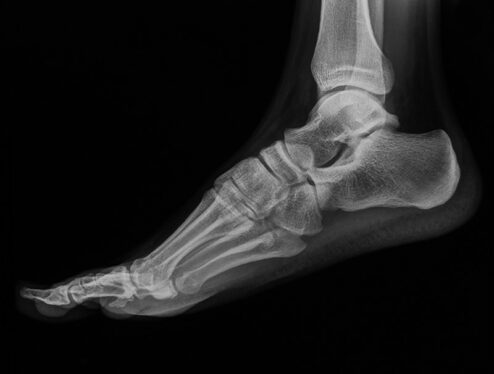

Lekarz oceni rozmiar kontuzji, między innymi wykonując zdjęcie rentgenowskie (RTG). Zwichnięcie wymaga nastawienia kości. Dalsza rehabilitacja zależy od rozległości urazu oraz indywidualnych cech pacjenta. Zasadą jest podzielenie fizjoterapii na etapy, w których kolejno następuje unieruchomienie stawu skokowego, po tym następuje przywracanie funkcji stawu, wreszcie etap przywracania aktywności.

Obrażenia tego typu dzielą się na złamania z przemieszczeniem kości lub bez przemieszczenia. Te pierwsze w zależności od wieku pacjenta są naprawiane operacyjnie. Te drugie są niekiedy trudne do rozpoznania nawet w badaniu obrazowym (RTG). Dlatego wśród osób uskarżających się na ból stopy zdarzają się przypadki zastarzałych złamań kości stawu skokowego. W większości przypadków do naprawienia tego stanu konieczna jest interwencja chirurgiczna.